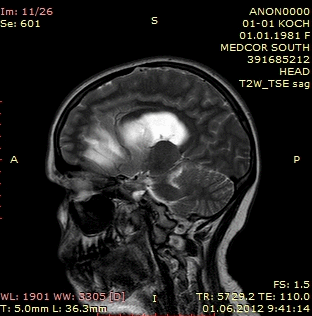

Ліпома мозку лікування, фото, прогноз

Пухлина жирової тканини, яка локалізується в підшкірній клітковині, діагностується без особливих труднощів. Такий діагноз лікар-онколог виставляє на підставі візуального огляду ураженої ділянки тіла. Ліпома, як правило, має вигляд округлого ущільнення шкірного покриву, температура якого трохи нижче прилеглих тканин епідермісу.

Для уточнення структури ліпомного ураження мозку, фахівці вдаються до ультразвукового дослідження, в ході якого лікар з'ясовує розмір, розташування і внутрішню будову новоутворення.

Діагностика ліпоми мозкових тканин проводиться за допомогою наступних методик:

Пошарове рентгенологічне сканування мозкових тканин дозволяє встановити точне розташування і форму доброякісного новоутворення. Даний діагностичний метод також надає інформацію про стан кровоносної системи в патологічній області. Це має суттєве значення в плані диференціальної діагностики ліпоми і злоякісної пухлини. Відмінною рисою жирової мутації є практично повна відсутність кровоносних судин в патологічному вогнищі.

Дане обстеження включає сканування головного мозку в зоні дії електромагнітного поля. Така процедура визначає найдрібніші зміни структури мозкової тканини.